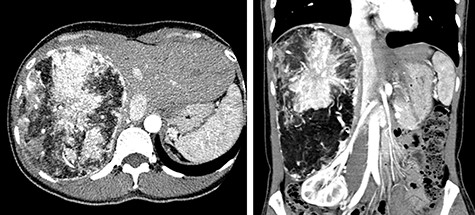

A 45-year-old woman was referred to our hospital with a huge liver tumor, which had been diagnosed as HAML 5 years previously when it was 12 cm in diameter (Fig. 1). Periodic follow-up with ultrasound and magnetic resonance imaging after the initial diagnosis had shown a progressive increase in the size of the tumor, and by the time of referral it measured 20 × 14 cm and had become symptomatic. On admission, enhanced computed tomography revealed a very large, well-defined, mixed-density mass occupying the entire right lobe of the liver (Fig. 2). Angiography showed dilated and tortuous vessel inside the tumor, and a drainage vein from the tumor to the right hepatic vein was visualized in the early phase (Fig. 3).

Abdominal CT on admission; the tumor had enlarged, occupying the entire right lobe of the liver, and measuring 200 × 140 × 120 mm.